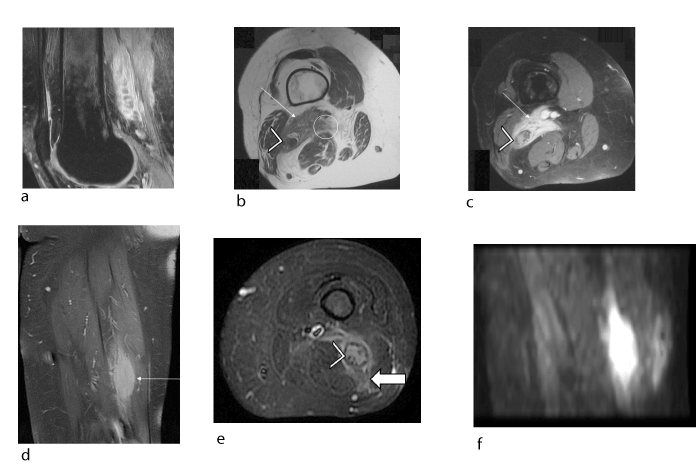

Figure 4. Female patient, 49 years old, lymphoma discovered (confirmed histologically) in the posterior area of the left thigh that invaded the sciatic nerve (a, b, c) during an assessment for knee pain. Intraneural metastasis of the contralateral sciatic nerve developed 1 year later (confirmed histologically) (d, e, f): (a) Sagittal proton density fat-saturated slice (TR/TE 2700/24) showing the tumour (arrow) with heterogeneous signal and tumour invasion (hyperintensity) of the sciatic nerve (arrow head) leading to dissection of the nerve fascicles (hypointense signal). (b) Axial T1 slice (TR/TE 440/11) showing an irregular-shaped tumour (arrow) with ill-defined margins (circle) in the posterior region of the left thigh over the path of the sciatic nerve (arrowhead). (c) Axial T1-weighted fat-suppressed post-gadolinium slice showing homogeneous uptake in the tumour (arrow) with dissection of the sciatic nerve fascicles (arrowhead). (d, e) Coronal and axial slices from proton density fat-saturated sequences (TR/TE 2700/24) showing a fusiform tumour (arrow) of the sciatic nerve with invasion of the adjacent soft tissues (solid arrow), evidence of hematogenous spread to the contralateral side. Note the dissection of the sciatic nerve fascicles (hypointense signal) by the hyperintense infiltrating tumour (arrowhead). (f) Sagittal slice from diffusion-weighted b800 sequence showing hyperintensity, which confirms the lymphatic origin of the tumour.